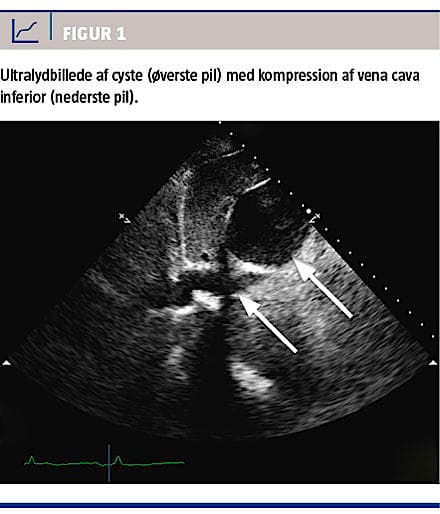

Der blev foretaget CT af thorax og abdomen med henblik på LE samt bekræftelse af cystens størrelse

og placering (Figur 2). Ved CT’en afkræftedes LE, men der blev konstateret en stor levercyste på 6 ×

10 × 7 cm, der komprimerede VCI med dillatation under cysten (Figur 2), samt at trombedannelsen strakte sig helt op i den distale VCI.